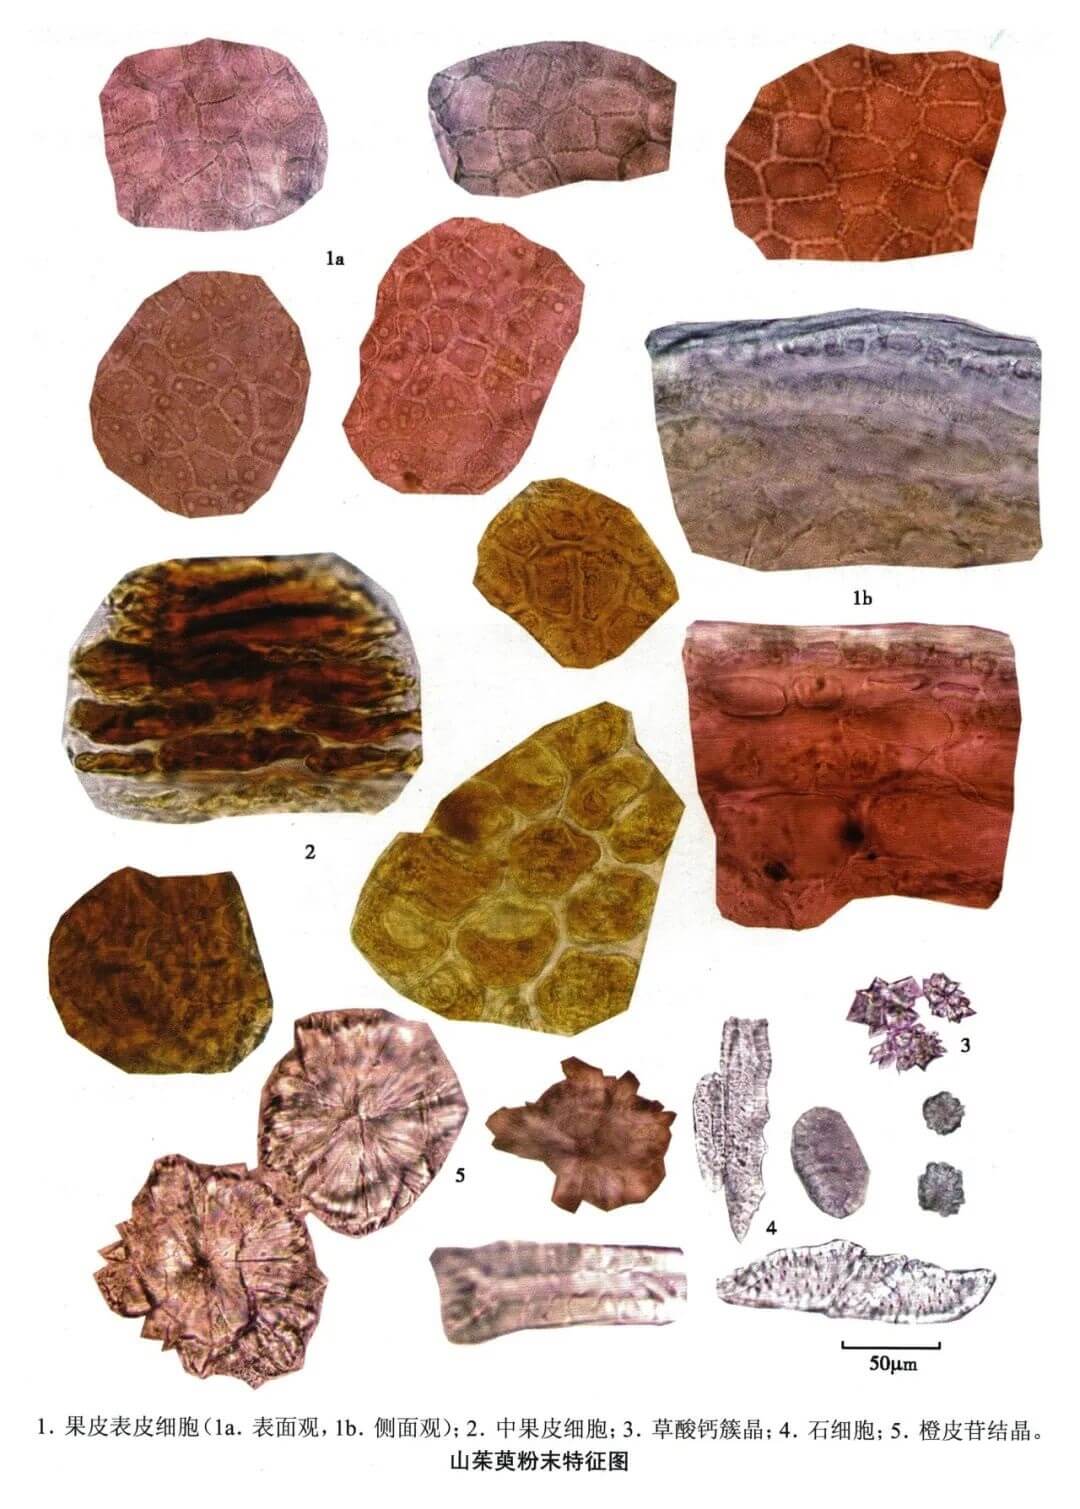

山茱萸

| 山茱萸 |

|---|

| 【参考标准】 《中国药典》2020年版 一部 |

| 【显微鉴别】 本品粉末红褐色。果皮表皮细胞橙黄色,表面观多角形或类长方形,直径16~30μm,垂周壁连珠状增厚,外平周壁颗粒状角质增厚,胞腔含淡橙黄色物。中果皮细胞橙棕色,多皱缩。草酸钙簇晶少数,直径12~32μm。石细胞类方形、卵圆形或长方形,纹孔明显,胞腔大。 |

| 【显微重点】 果皮表皮细胞、橙皮苷结晶。如果样品是茱萸肉,则观察不到石细胞。 |

| 【图谱来源】 《中药成方制剂显微图典》 |